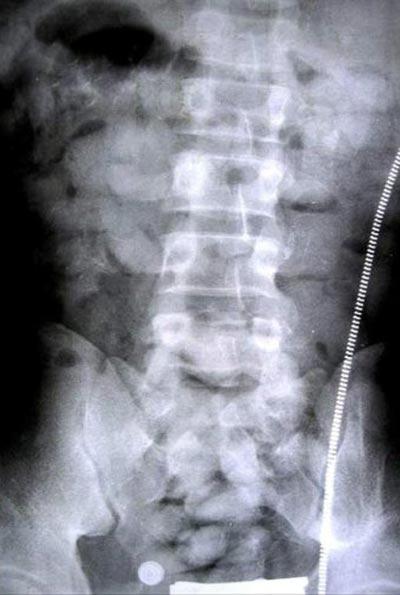

На фото можно увидеть рентгеновский снимок Чарли, в организм которого хирургическим путем было вживлено 150 пакетиков с белым порошком.